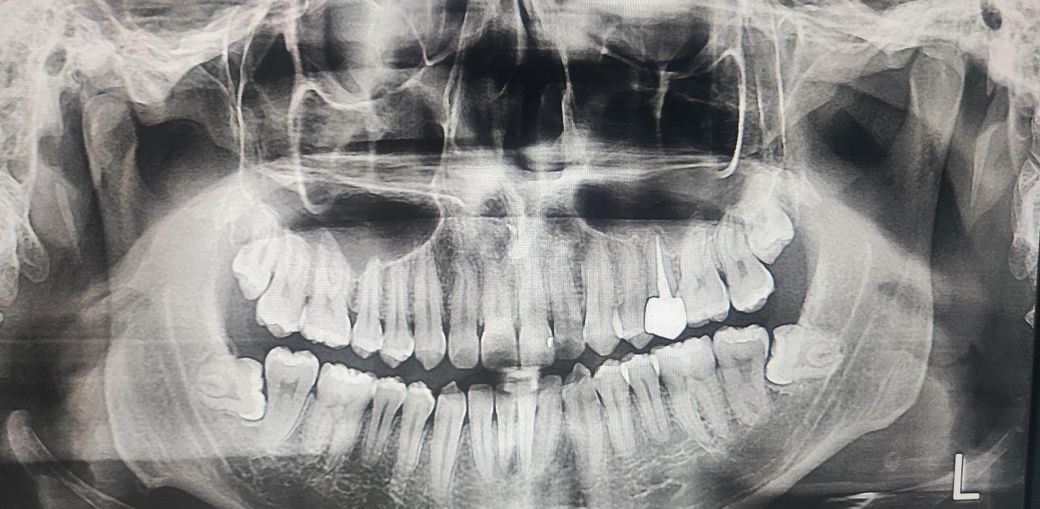

소구치 재신경치료 후 옆으로 밀면통증

좌측 2소구치 재신경치료한지 1년 지났어요

치료 직후랑 1년후랑 증상이 같아요 호전도없고 악화도 없고

씹을때 문제없고 옆으로 밀 때, 이빨끼리 딱딱 부딪힐때 울림이 느껴지면서 예민함이 느껴지는데 잇몸 문제나 교합문제 일 수 있나요? 가끔 어느날은 옆으로 밀거나 건드려도 통증 없는 날도 있습니다. 가끔이지만요. 이번에 크라운 떼게 된다면 남아있는 치아가 거의 없어 임플란트를 해야합니다 ㅜㅜ 이거 1년이나 지났지만 시간이 지나면서 나을 수 있을까요?

• 1번 째 사진

엑스레이상 신경치료는 잘 마무리 되어 있는 것 같은데 혀로 밀었을때 불편감이 있는 것은 대체로 미세한 잔존 신경이 있어서 그렇습니다 재신경치료보다는 치근단절제술, 의도적재식술로 가야할 것 같습니다